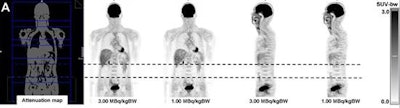

FDG-PET images show good image quality in a 43-year-old patient with a dose of 1 MBq/kgBW (A). However, there was an artifact in the abdominal region (B) at lower doses. This region was located completely within one bed position (dotted line). Images courtesy of JNM.

FDG-PET images show good image quality in a 43-year-old patient with a dose of 1 MBq/kgBW (A). However, there was an artifact in the abdominal region (B) at lower doses. This region was located completely within one bed position (dotted line). Images courtesy of JNM.Interestingly, the readers considered most PET images with FDG doses of 1.25 to 2.75 MBq/kgBW to be just as good as those with 2 MBq/kgBW. One PET image with 2.75 MBq/kgBW and nine PET images with 3 MBq/kgBW were rated as substantially better.